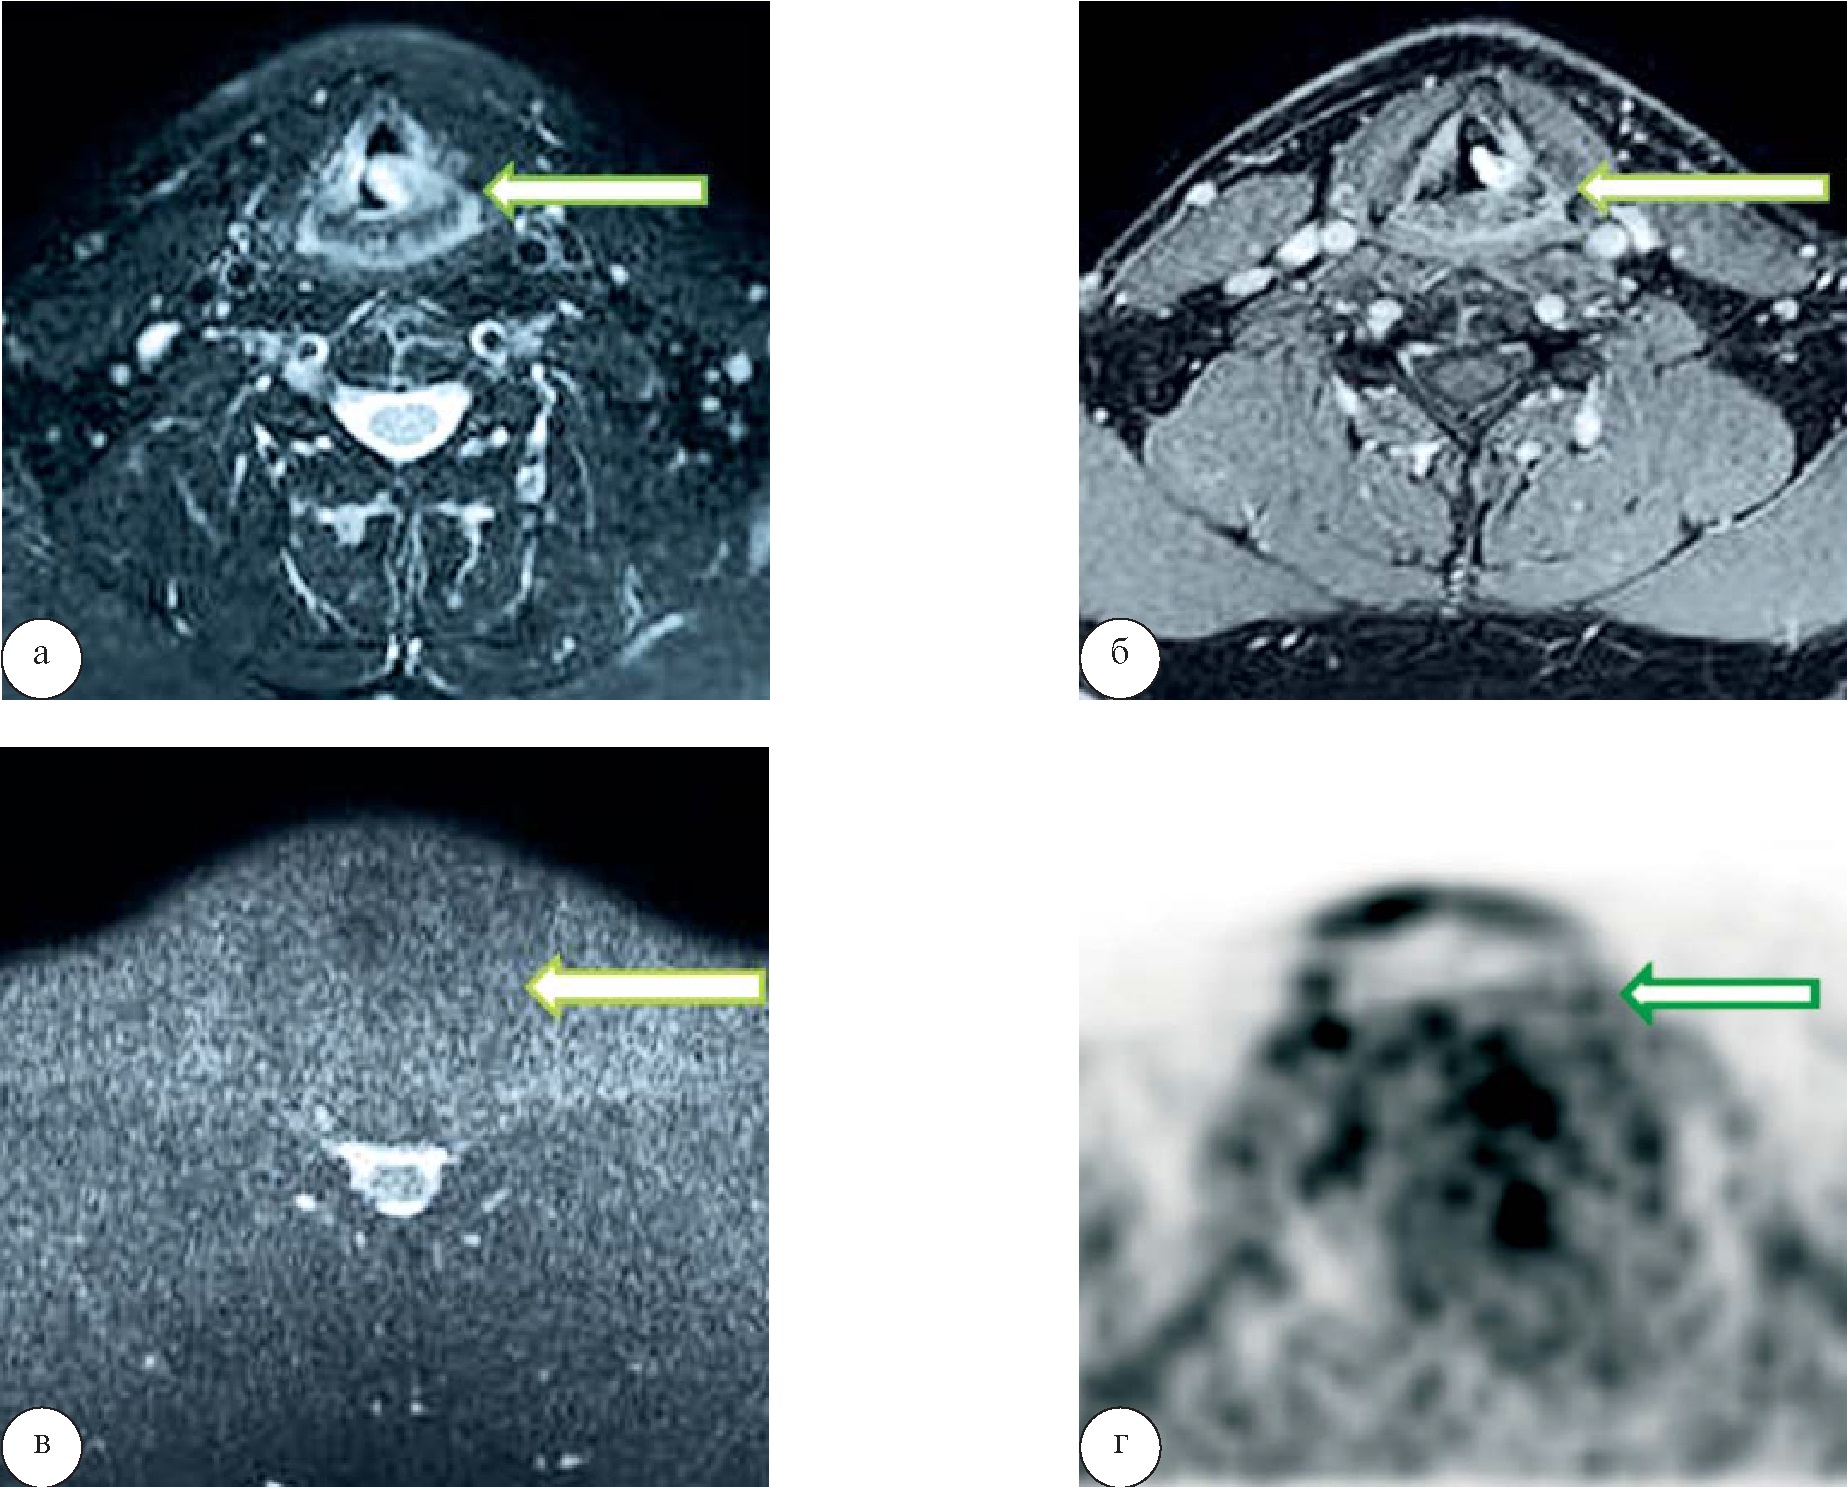

В третьей группе у 2 (3,7%) человек также в области выявленной опухоли, изоинтенсивной на ДВИ, прослеживался гиперметаболизм глюкозы (SUVmax 15,7) без сопутствующей лимфоаденопатии (рис. 6). Еще у 2 (3,7 %) пациентов в этой группе гиперфиксации РФП в области образования повышения сигнала на ДВИ не отмечалось, что было расценено как доброкачественные образования с последующей гистологической верификацией опухолей – фиброма и гемангиома (рис. 7).

Рис. 6. Рак голосовой связки. При МРТ на Т2-ВИ (а) отмечается образование правой голосовой складки, характеризующееся неоднородным гиперинтенсивным сигналом, изоинтенсивное при МР-диффузии, без повышения сигнала на b=800 (б). Однако при выполнении ПЭТ/КТ (в) в области образования правой голосовой складки определяется гиперметаболизм 18-ФДГ

Рис. 7. Фиброма гортани. При МРТ на Т1-ВИ (а) и Т2-ВИ (б) определяется образование, расположенное над левой голосовой складкой, с распространением на левую черпалонадгортанную складку, прилежащее к черпаловидному хрящу (стрелка). Образование накапливает контрастное вещество преимущественно в периферических отделах и не имеет гиперинтенсивного сигнала на ДВИ (в) (стрелка). На ПЭТ-изображении гиперметаболизма глюкозы в области образования не выявлено (г) (стрелка)